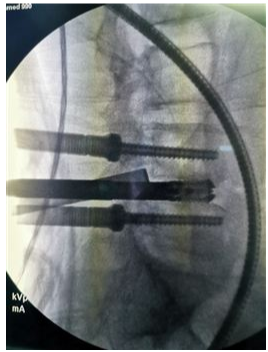

奧蘇本UBE技術(shù)概UBE技術(shù)即單側(cè)雙通道內(nèi)鏡技術(shù)(Unilateral Biportal Endoscopy Technique),適用于頸椎、胸椎、腰椎的退行性病變。與椎間孔鏡的單通道不同,該技術(shù)通常建立兩個(gè)通道,一個(gè)為觀察通道,一個(gè)為器械操作通道。觀察通道一般會(huì)用到0°或30°UBE內(nèi)鏡,操作通道使用UBE專器械,如UBE刮匙、磨鉆(UBE內(nèi)鏡磨頭)、UBE內(nèi)鏡刨刀、UBE內(nèi)鏡消融電極、UBE椎板咬骨鉗、UBE髓核鉗、UBE神經(jīng)拉鉤等。UBE技術(shù)的專用器械包,通過(guò)UBE技術(shù)還可以完成鏡下融合手術(shù)。

該技術(shù)開(kāi)展脊柱手術(shù)時(shí),克服了中心管狹窄、側(cè)管狹窄和椎間孔狹窄的局限。手術(shù)入路角度范圍廣,在不損傷脊柱結(jié)構(gòu)完整性的前提下,有效地對(duì)椎管進(jìn)行了周向和局部減壓,保留了肌肉韌帶附著通過(guò)肌間間隙,保護(hù)背支內(nèi)側(cè)支,從而防止?fàn)繌垞p傷。這種內(nèi)窺鏡入路允許從對(duì)側(cè)后入路和孔外入路(椎旁孔外入路)進(jìn)入孔,為治療所有類型的狹窄提供了靈活性,因此,UBE技術(shù)作為一種微創(chuàng)的融合方法,具有極強(qiáng)的實(shí)用性。

6、適應(yīng)癥廣泛,能輕松完成鏡下融合、頸椎、胸椎、腰椎等復(fù)雜病例。